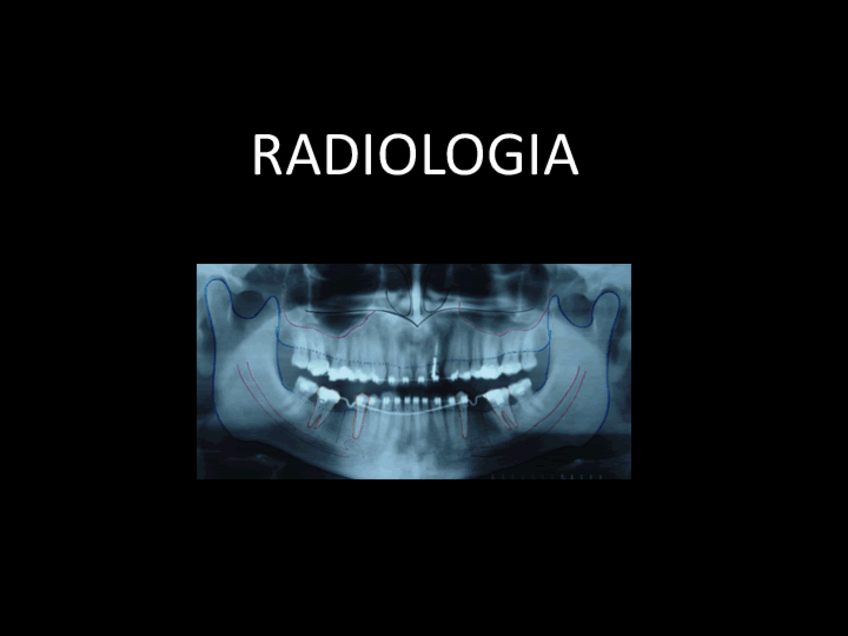

Radiologia.pdf